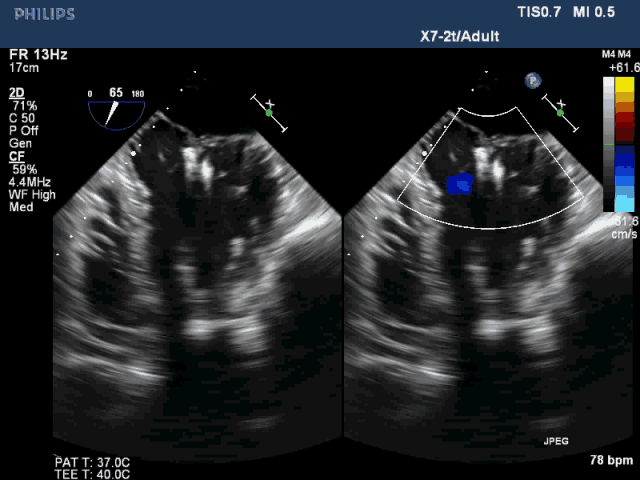

图2 术前食道超声显示二尖瓣大范围脱垂及极重度反流

图3 植入双夹合器后反流为轻度

该例患者是一名78岁男性,合并症较多,基础心功能差,传统外科手术风险极高,故选择了经心尖二尖瓣夹合术(ValveClamp)。然而,术前超声评估显示,患者后叶脱垂范围极大,达23mm,P2 和P3均有脱垂,反流颈宽度达13mm。严重二尖瓣反流导致患者心功能很差,血压较低。如此广泛的脱垂,使用国外同类产品完成经导管微创二尖瓣修复也是很有挑战,甚至无法完成的。葛均波院士团队分析患者病情后,选择了使用我国自主研发的二尖瓣器械ValveClamp为患者实施经心尖二尖瓣夹合术。反复尝试数次单个夹合器夹合后,患者仍有中重度二尖瓣反流。遂采取双夹合器技术,为患者植入两个夹合器,术后即刻患者反流减少至轻度,二尖瓣跨瓣压差仅为3mmHg。该例手术是ValveClamp首例采取双夹子技术,证明了该器械行双夹子技术是安全、可行的。手术由中山医院心内科葛均波院士、周达新教授、潘文志副主任医师,心外科魏来教授,心超室的潘翠珍教授、李伟主治医师,心外麻的郭克芳教授共同完成。